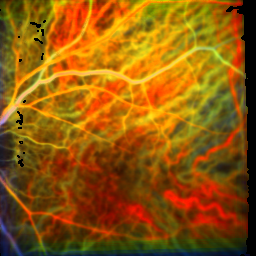

Responder

before the first rheopheresis after the first rheopheresis after the third rheopheresis

time of the maximum: 55.4 f ± 10.1%

visual acuity: 0.50

time of the maximum: 53.3 f ± 14.5%

visual acuity: 0.63

time of the maximum: 34.7 f ± 13.8%

visual acuity: 0.80